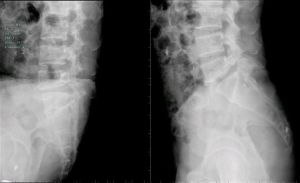

正位X線片常顯示腰椎輕度側彎,關節突間關節間距離變小,有退行性改變。側位X線片顯示椎管中央矢狀徑常小,小於15mm就說明有狹窄的可能。必要時可進行腰椎穿刺,奎肯試驗,腦脊液化驗,及脊髓造影。脊髓造影是診斷本症的可靠方法。正位片可清楚顯示硬脊膜腔的大小,如出現有條紋狀或鬚根狀陰影,表示馬尾神經根有受壓現象,或全梗阻,如影柱呈節段性狹窄或中斷,表示為多發性或全梗阻。

CT、MRI檢查:鞘膜囊和骨性椎二者大小比例改變,鞘膜囊和神經根受壓,硬膜外脂肪消失或減少,關節突肥大使側隱窩和椎管變窄,三葉狀椎管,弓間韌帶、後縱韌帶肥厚。

1975~1977年Verbiest根據椎管中央矢狀徑(m-s徑)和椎管椣徑的測量將椎管狹窄分為三型:

即椎管的中央矢狀徑小於或等於10mm者,為絕對型椎管狹窄(m-s≤10mm)。

即椎管的中央矢狀徑小於或等於10~12mm者(m-s為10~12mm)較多。

總之中央矢狀徑(m-s徑)小於11.5mm由肯定為病理現象。如腰椎管的頭側或尾側的中央矢狀徑比值大於1則為異常現象(頭尾正常時m-s徑之比值小於)。

橫徑:即椎弓根最大距離,平均值為23mm。其正常值下限為13mm(X線照片為15mm)。